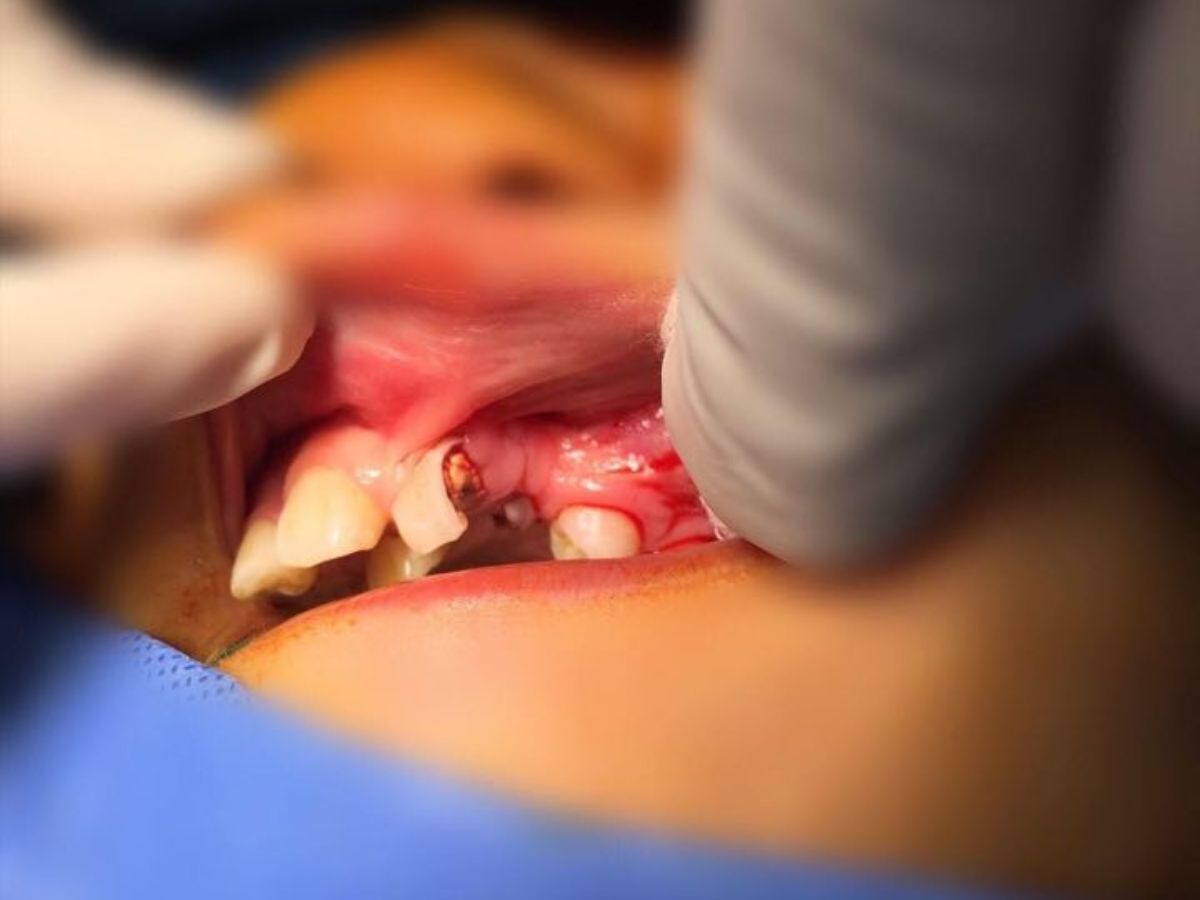

- Đánh giá và chuẩn bị trước phẫu thuật: Những răng sữa mọc lệch vào vị trí khe hở có thể được chỉ định nhổ bỏ trước khi tiến hành ghép xương nhằm tạo không gian thuận lợi cho quá trình tái tạo xương.

- Tạo vạt niêm mạc vùng khe hở: Bác sĩ rạch niêm mạc miệng dọc theo hai bờ khe hở, sau đó phẫu tích để tạo vạt niêm mạc mũi và vạt niêm mạc miệng, giúp chuẩn bị nền mô mềm cho việc đặt xương ghép.

- Đóng vết mổ: Vùng khe hở được khâu đóng theo hai lớp niêm mạc, bao gồm lớp niêm mạc mũi phía trên và lớp niêm mạc miệng phía dưới, trong khi khối xương ghép được giữ ổn định ở giữa.